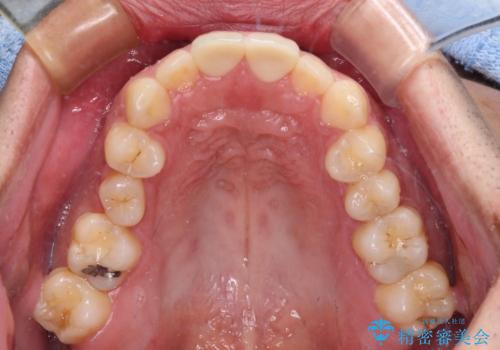

歯が欠けるほどの強い衝撃を受けると、歯根が溶けてしまう外部吸収という現象を起こすことがあるため、補綴治療後しばらく様子を見ておりましたが、何と三度自転車事故に遭いかけてしまいました。